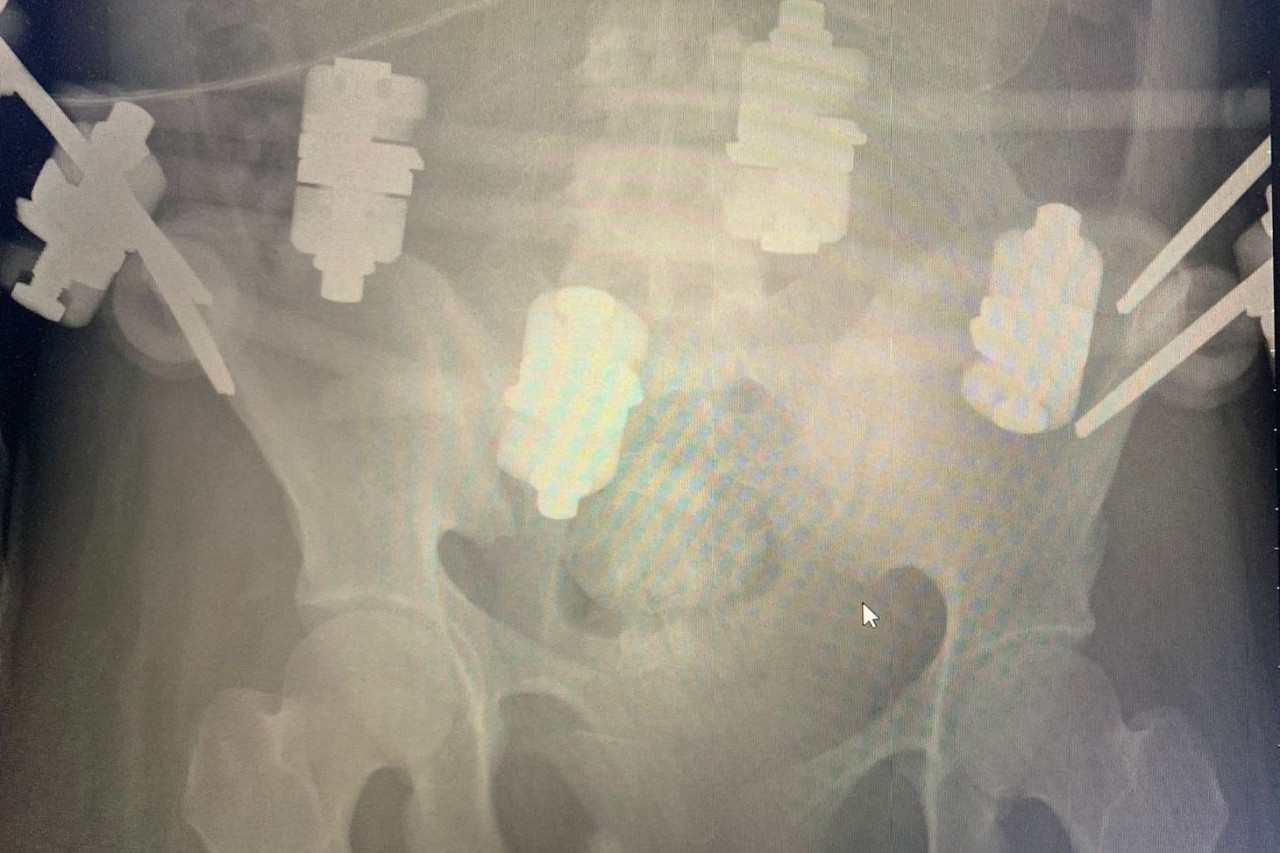

Рентген-снимок костей таза

Молодая девушка из Калининградской области рано потеряла маму, воспитывал ее вместе с тремя младшими детьми папа. Однако новая трагедия, случившаяся в канун Нового 2023 года, снова разделила жизнь семьи на «до» и «после». Машина, в которой 19-летняя калининградка ехала с дядей, попала в страшную аварию — из-за метели легковушку занесло под грузовик. Дядя погиб сразу, а девушку в крайне тяжелом состоянии, с черепно-мозговой травмой, с оскольчатым переломом крестца и правой лонной кости со смещением экстренно доставили в Калининградскую областную больницу в состоянии комы. На тот момент она была в положении — срок беременности составлял 20 недель. В Калининграде врачам удалось сделать операцию по восстановлению тазовых костей с имплантацией спиц. Однако из-за того, что беременная была лежачей, на искусственной вентиляции легких (с трахеостомой), у нее развилась пневмония. Инфекция стала быстро распространяться по всему организму и поразила даже установленные металлоконструкции в тазу.